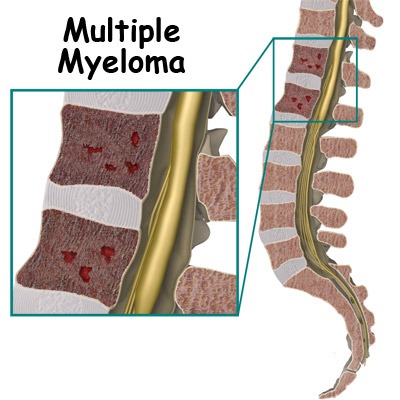

بیشتر بخوانید »همه چیز درباره سرطان مولتیپل میلوما

میلوم مولتیپل (Multiple Myeloma) شایعترین تومور استخوان یا سرطان استخوان است که منشا آن از خود استخوان بوده و از جای دیگر نیامده است. به تومورهایی که منشا آنها سلول های خود استخوان است تومور اولیه استخوان می گویند. سن شیوع این تومور بالای 40 سالگی است و در مردان بیشتر است. میلوم مولتیپل چگونه ایجاد می شود؟ این تومور …